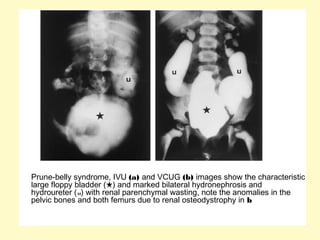

Prune-belly syndrome, IVU (a) and VCUG (b) images show the characteristic

large floppy bladder (★) and marked bilateral hydronephrosis and

hydroureter (u) with renal parenchymal wasting, note the anomalies in the

pelvic bones and both femurs due to renal osteodystrophy in b

Prune-belly syndrome, IVU(a) and VCUG (b) images show the characteristic large floppy bladder (★) and marked bilateral hydronephrosis and hydroureter (u) with renal parenchymal wasting, note the anomalies in the pelvic bones and both femurs due to renal osteodystrophy in b